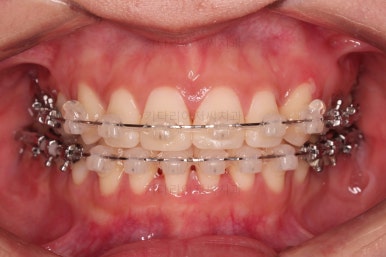

어느새 틈도 다 닫히고요.

마무리 과정만 남았습니다.

4. 마무리

틈이 다 없어졌고, 교합도 양호합니다.

무엇보다 임플란트 없이 결손부위가 깔끔하게 채워졌고요.

매우 다행으로 사랑니도 다 있었기 때문에 마치 큰 어금니가 다 있는 것과 같은 상황이 되었습니다.